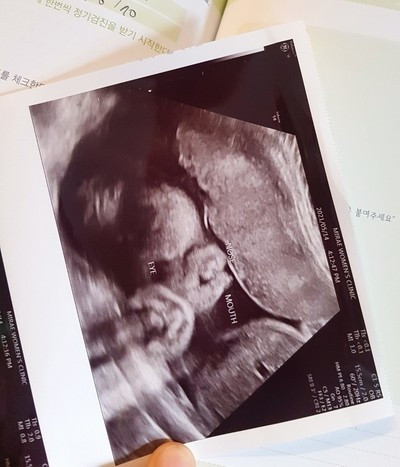

"사랑이에게 인사하세요."

은서 씨가 임신 초기, 가까운 지인들에게 초음파 사진을 보내며 덧붙이던 인사이다. 열무, 튼튼이, 딱풀이 등 다양한 태명 후보가 많았지만 결국 은서 씨가 선택한 태명은 '사랑이'였다.

"왜 그런 말 있잖아요. 드라마나 영화는 제목따라 가고, 가수는 노래 제목 따라 간다는 말. 그 말처럼 우리 아이도 사랑을 많이 받았으면 하는 마음으로 지은 태명이예요. 기분 탓일 수도 있지만 이름 덕인지 주변에서도 사랑이를 많이 예뻐하는 것 같아 잘 지었다고 생각해요. 아예 이름도 사랑이라고 지어줄까 고민될 만큼요."